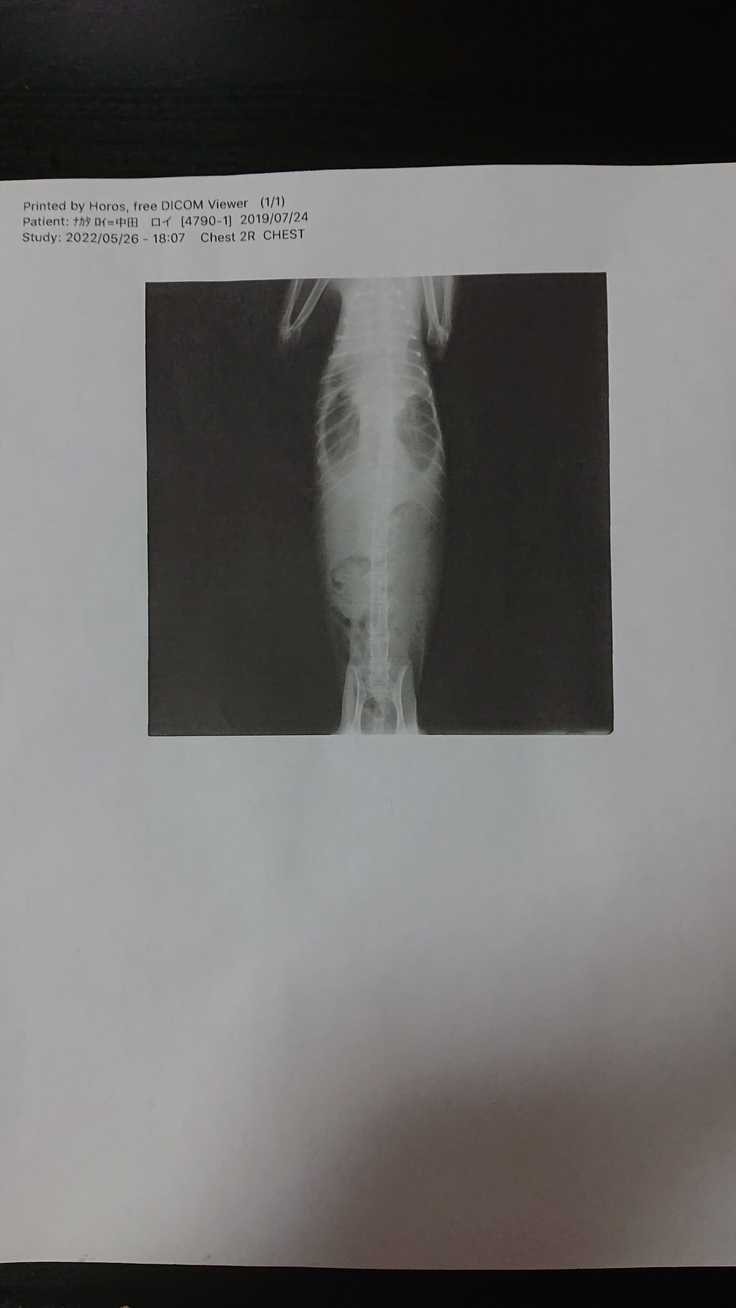

ロイは胸水と腹水が溜まっており、リンパ節にも炎症があることから混合タイプと診断されました。

その後しばらく様子を見たものの食欲は少し戻りましたが以前程元気にはなりませんでした。そして呼吸を苦しそうにするようになったので慌てて病院に連れていきました。そこでレントゲンを撮ると胸とお腹に水が溜まっており、かなり危険な状態だと先生から告げられました。

そしてその場で胸水だけ抜いてもらい、その胸水が黄色くて粘りがあり、ロイの症状からもFIPでほぼ間違いないだろうと言われました。

<血液検査の結果>

貧血の度合いを示す赤血球容積比の数値が低く混合タイプの中後期だろうと診断され、かなり危険な状態であったため入院し、注射による投薬治療を開始しました。